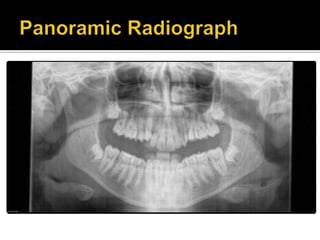

Medical History: denied any medical problems.

All teeth are present

Impacted upper and lower 8’s.